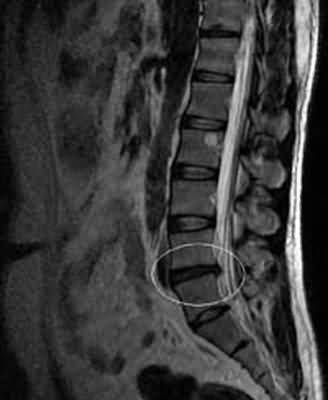

Диагностика

Секвестрированная и обычная грыжа четко проявляется на рентгенологическом снимке. При пальпации пораженного участка позвоночника боли усиливается, визуально врач видит патологическую осанку, приобретенную по мере развития грыжи межпозвоночного диска. На рентгенографическом исследовании специалист может выявить грыжу в начальной стадии – протрузии, тогда еще возможно провести консервативное лечение.